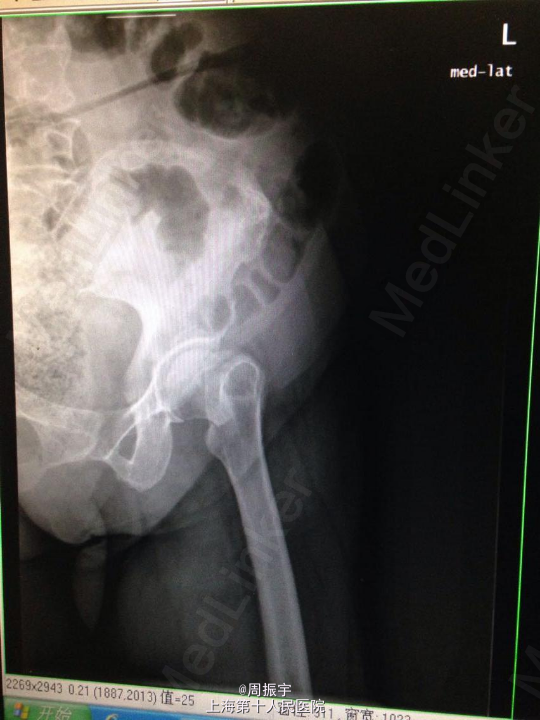

查体:患者发病以来精神可,胃纳差,睡眠差,大小便正常,体重无明显减轻。 左下肢短缩外旋畸形,左髋未见红肿及皮肤破损。左髋压痛(+),左下肢纵向叩击痛(+),足背动脉搏动好。左髋活动明显受限,左膝活动无受限、左踝及足趾活动无异常,左足背动脉搏动好。左下肢较右下肢稍缩短约1cm。余肢体均正常。 辅查:X线:左股骨颈骨折。 骨盆正位数字化摄影 , 检查诊断:左侧人工髋关节置换术后。右髋关节退变,右股骨头坏死可能,请结合临床。

诊断:左股骨颈囊内骨折(Garden IV型) 治疗经过:患者入院后完善各项检查,明确诊断,积极术前准备,全麻下行左侧全髋关节置换术,术顺。